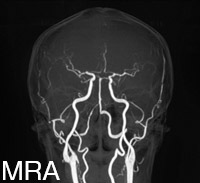

MRA

脳血管の様子(脳動脈瘤や狭窄、閉塞など)